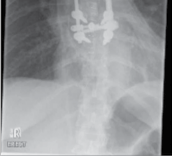

Clinical & Radiographic Imaging Archive